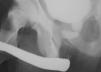

Caso 3. Varón de 12 años, traumatismo pélvico (por aplastamiento) y rotura uretra prostática (fig. 2). Realineación primaria endoscópica. Uretrotomía interna endoscópica a los 5, 6, 9 y 14 meses PO. Litotricia transuretral por desarrollo de litiasis vesical a los 5 y 18 meses. Uretroplastia T-T a los 2 años PO y, por reestenosis, uretroplastia transpúbica a los 3 años PO. Tras 14 años PO, incontinencia y eyaculación retrógrada.